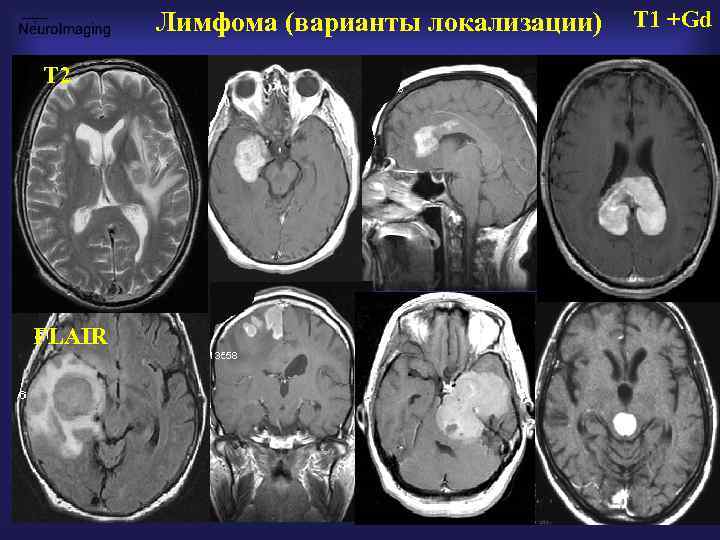

Лимфома (варианты локализации) Т 2 FLAIR T 1 +Gd